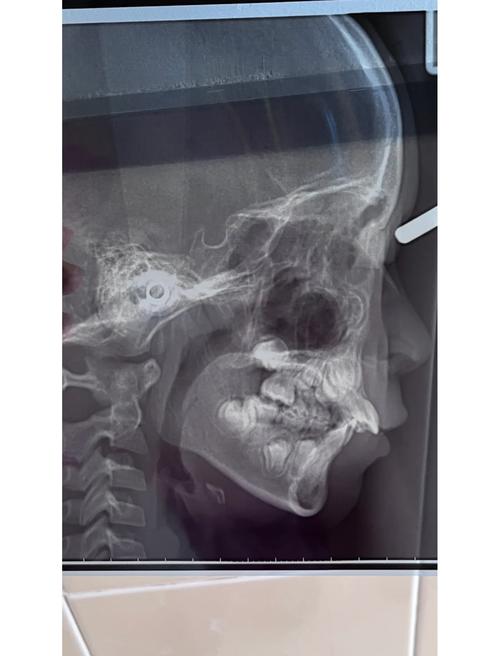

| 头颅侧位片 | 分析颅面骨骼的形态、位置关系(如SNA角、SNB角、ANB角),评估面部软组织轮廓,判断骨性畸形类型 | 骨性错颌畸形诊断,制定拔牙方案,预测矫正后面型变化 |